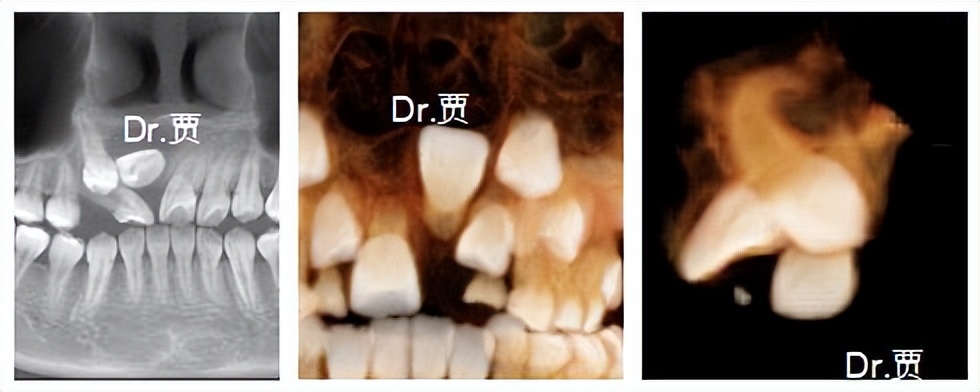

如果孩子门牙老不长,家长们一定要及时带孩子就医,通过拍摄牙片,排查迟萌的原因,有时候你以为它只是迟到了,实际上它可能迷路了。

发现问题后,正畸医生经过诊断分析,通过开窗牵引等正畸方式进行治疗,帮助牙宝宝找到正确萌出的路。